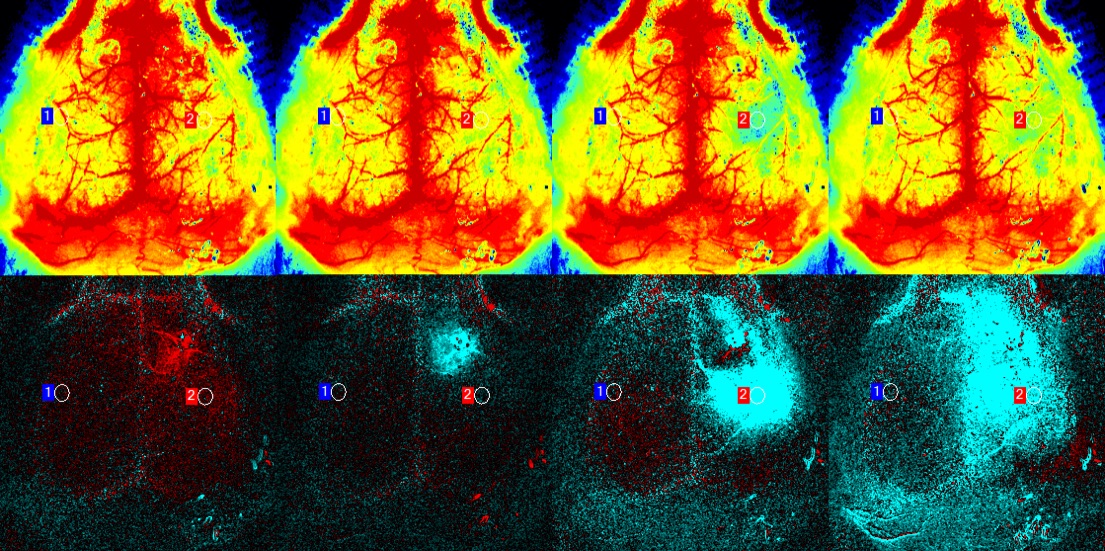

对SD的反向神经血管反应的观察发现扩散灌注缺陷导致SD延长(Dreier 2011)。激光散斑对比度分析 (LASCA 或 LSCI) 是区分正常(图1)与反向神经血管对SD的反应(图2)的理想工具,因为它可以显示空间和时间的灌注变化,并且很容易和测量SD或其他变量(例如氧的组织分压)的各种电生理学方法联合使用。

PeriCam PSI激光散斑成像系统可用于测量血管生成测定中血液灌注的变化,并检测各种促血管生成化合物的功效差异。它也可以用于监测功能性肿瘤内血管的形成,并评估抗血管生成剂在癌症治疗中的有效性。

PeriCam PSI每秒最多可测量100张图像。这样就可以以高图像质量看到快速的动态变化,例如心跳引起的搏动。